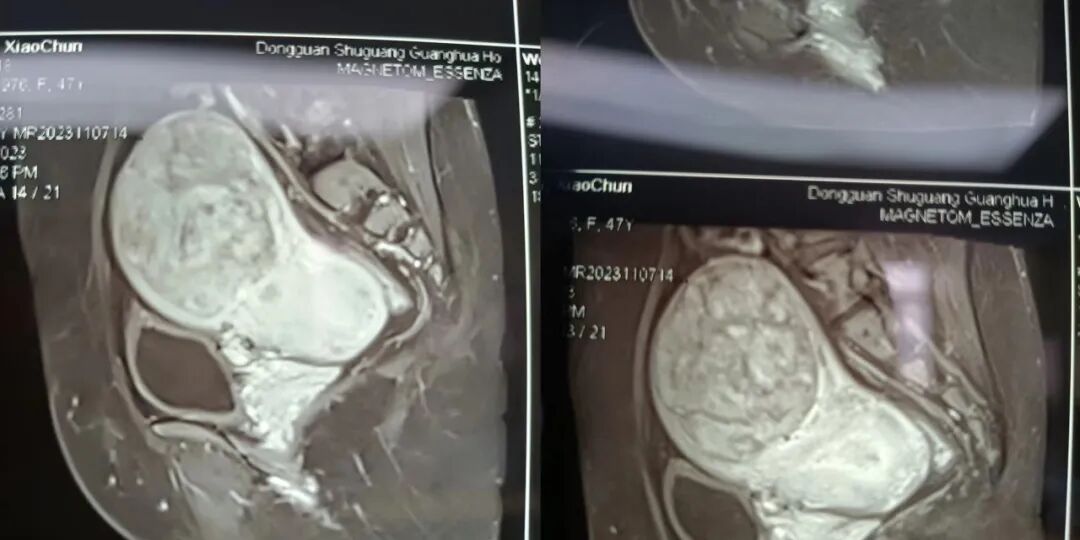

近日,我院妇产科收治一例患者,魏某某,女性,47岁,因发现子宫肌瘤两年余,近期自觉腹部增大,遂来我院妇科门诊检查。妇专科检查示:子宫体不均匀增大如孕5+月大小,子宫前壁靠近宫底部触及大小约100mm*100mm质硬包块。核磁共振提示患者的子宫肌瘤大约110*73*90mm大小,收住我科。完善相关检查,手术指征明确,需进行手术治疗。

术前,进行手术方式的论证:

像这么大的“巨瘤”切除术目前采取传统开腹手术会顺利些,但谢春玲主任考虑到传统开腹需在腹部切一长约10cm的切口,创伤大,术后恢复慢,住院时间长;经过反复论证和推演,最终决定在腹腔镜下进行微创手术,只需要在腹部切出3-4个0.5-1cm的切口即可完成,手术创伤小,恢复快,但手术难度及风险大,对手术者的要求非常高。

全科医护团队积极为患者完善所有术前准备,在谢春玲主任的带领下手术如期进行。无影灯下,谢春玲主任小心翼翼地将肌瘤分离、切割、捣碎、止血、精细解剖、精准切除,麻醉效果也安全稳定,手术室护理团队的配合也专业干练,最终顺利的将“巨瘤”完整切除掉。